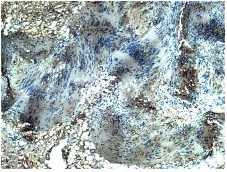

Postoperative period was uneventful. HPE showed a well circumscribed tumor composed of cellular Antoni A areas and Antoni B areas with areas of hyaline & cystic degeneration & ischaemic necrosis (Figure 4).

Figure 4- HPE of schwannoma: showing tumor composed of cellular Antoni A areas and Antoni B.

Histopathology of schwannomas consists of compact cellular areas (Antoni A) along with loose hypocellular myxoid stroma with microcystic spaces (Antoni B). Malignant schwannomas are characterized by high mitotic index, cellular pleomorphism and vascular and adjacent tissue infiltration. They behave like high grade sarcomas with local recurrence and distal metastasis. Immunohistochemistry is important for confirmation of diagnosis and also for ruling out malignancy. In Schwannomas there is a diffuse positivity for S 100 protein in cytoplasm of these cells.Vimentin is used as a sarcoma tumor marker to identify mesenchymal tissue.